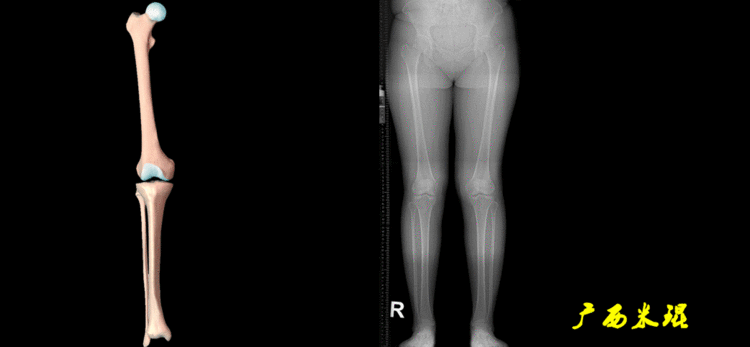

最常见的下肢畸形发生于冠状面,即膝内外翻畸形,冠状面的对线异常通过应用“对线异常检验”进行分析,机械轴的偏移(MAD)表现为对线异常。

膝内翻是指下肢力线通过膝关节中心点内侧,距中点2mm以上,偏内超过15mm为显著膝内翻。膝外翻是指下肢力线通过膝关节中心点外侧,距中点2mm以上,偏外超过10mm为显著膝外翻。